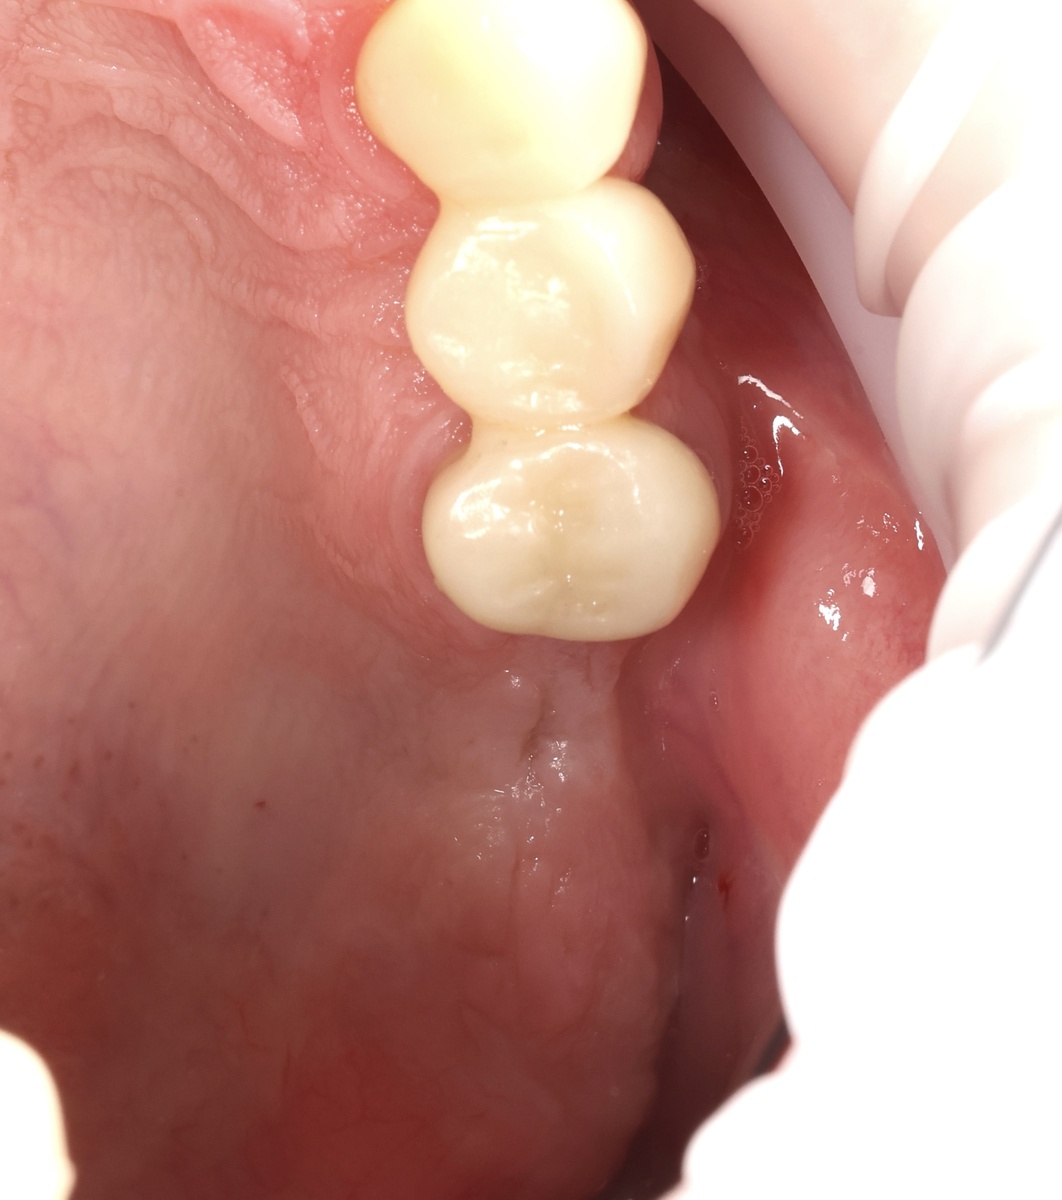

Сентябрь - циркониевые коронки винтовой фиксации

На оба импланта установили циркониевые коронки винтовой фиксации.

Фото:

Всё. Левая сторона работает. Можно жевать. На "черные" корни под старыми коронками можно не особо смотреть сейчас, их никак не реанимировать, а удалять тоже не время - пациент не готов и это допустимо в данном случае.